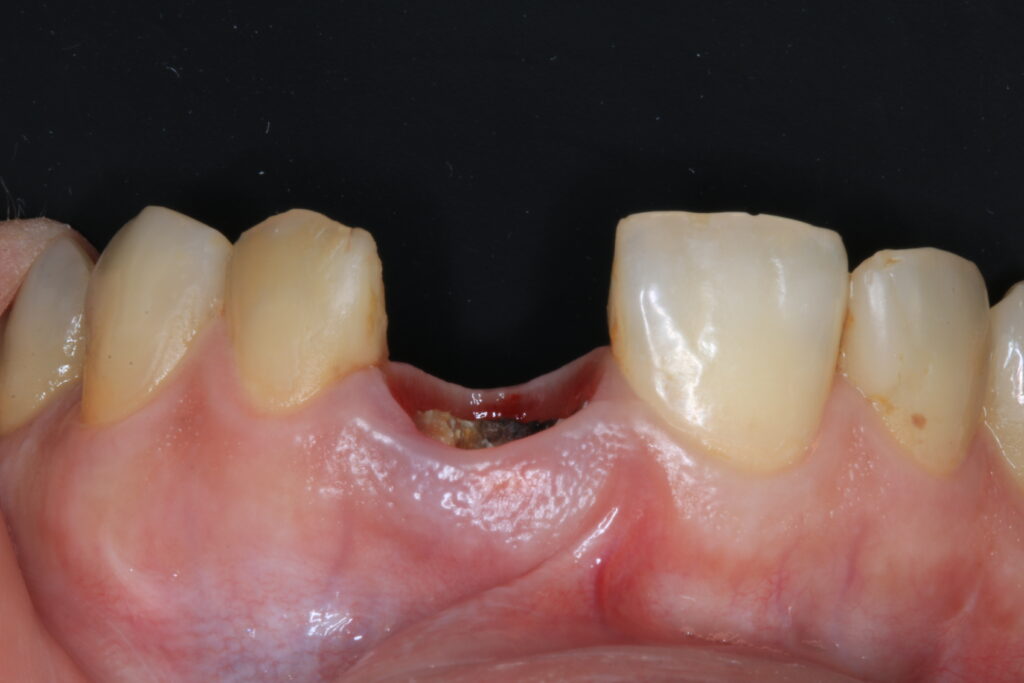

Fig. 1b: Initial situation with non-restorable tooth 21